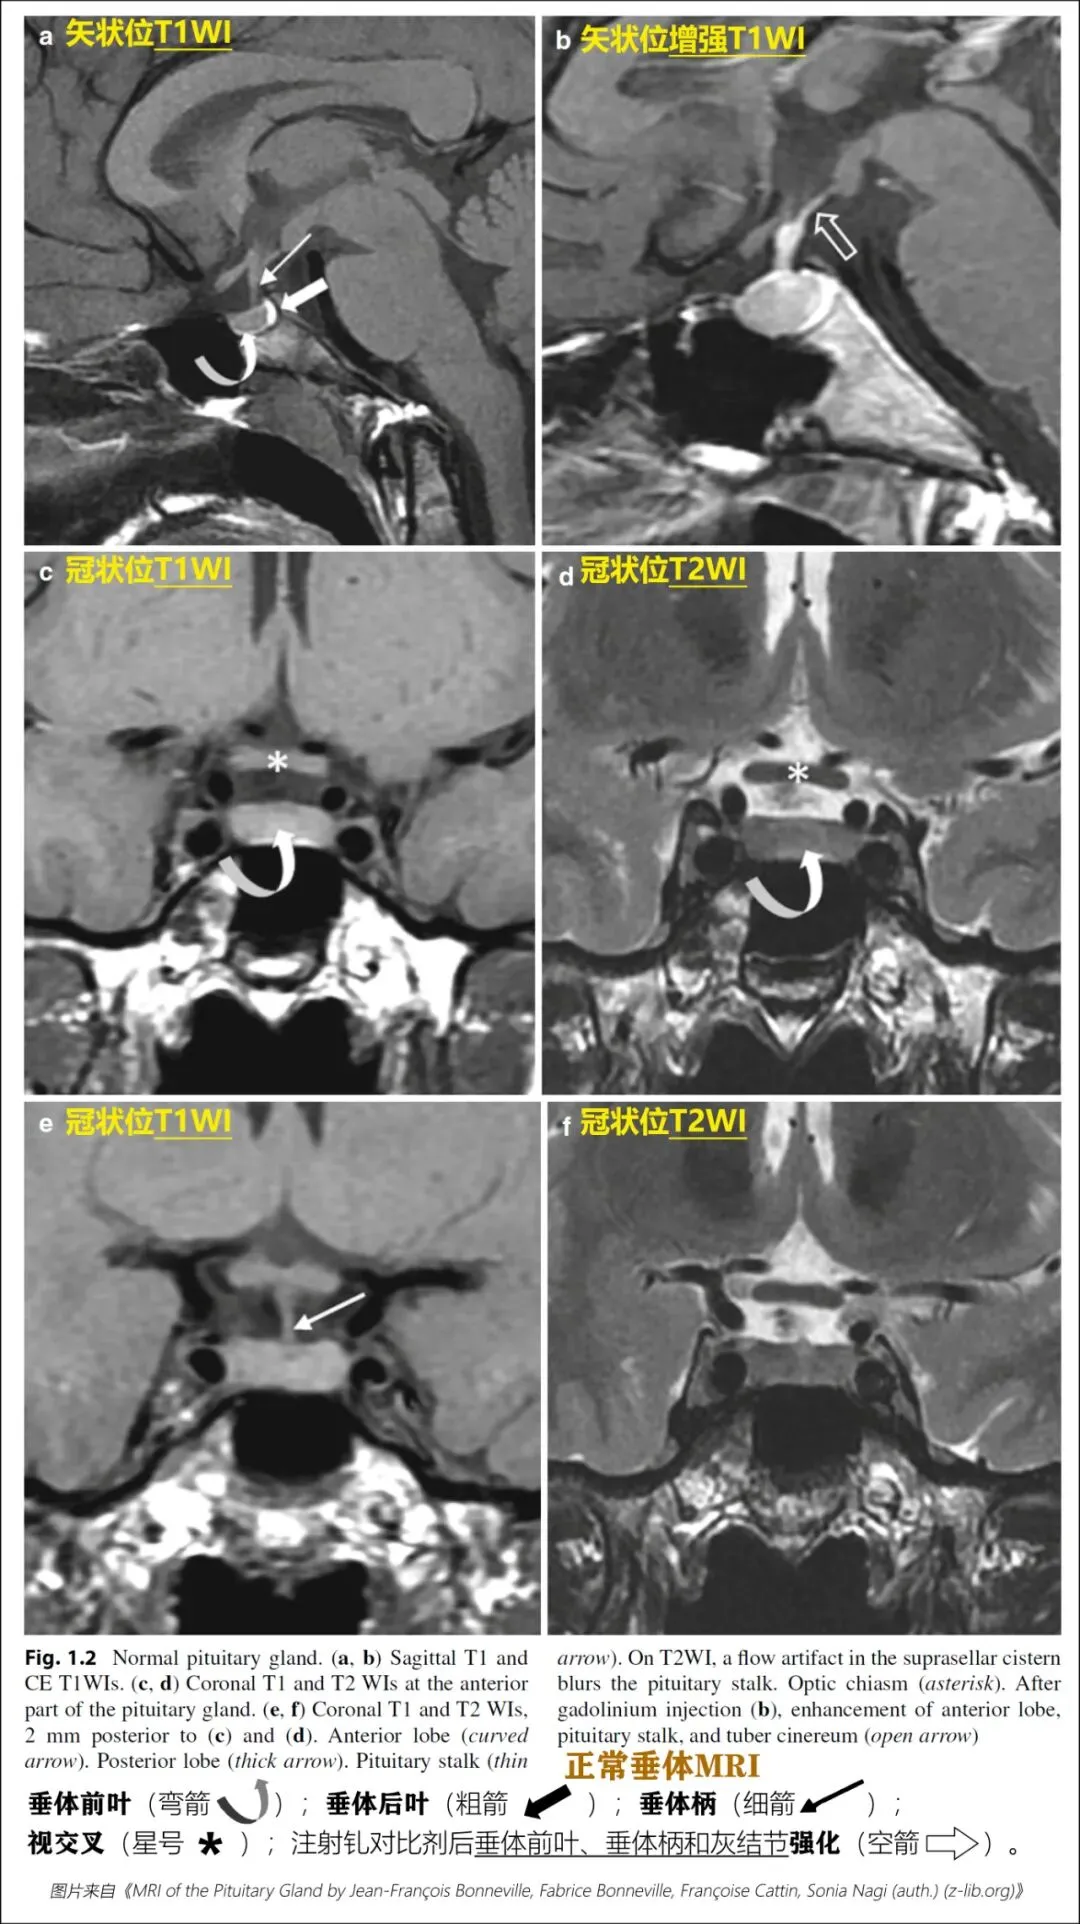

垂体前叶主要由门脉供血,动态成像上,前叶强化晚于后叶。

注射轧对比剂后20-30秒:垂体柄及垂体上部强化。

注射轧对比剂后40-60秒:垂体显著强化,之后信号缓慢下降。